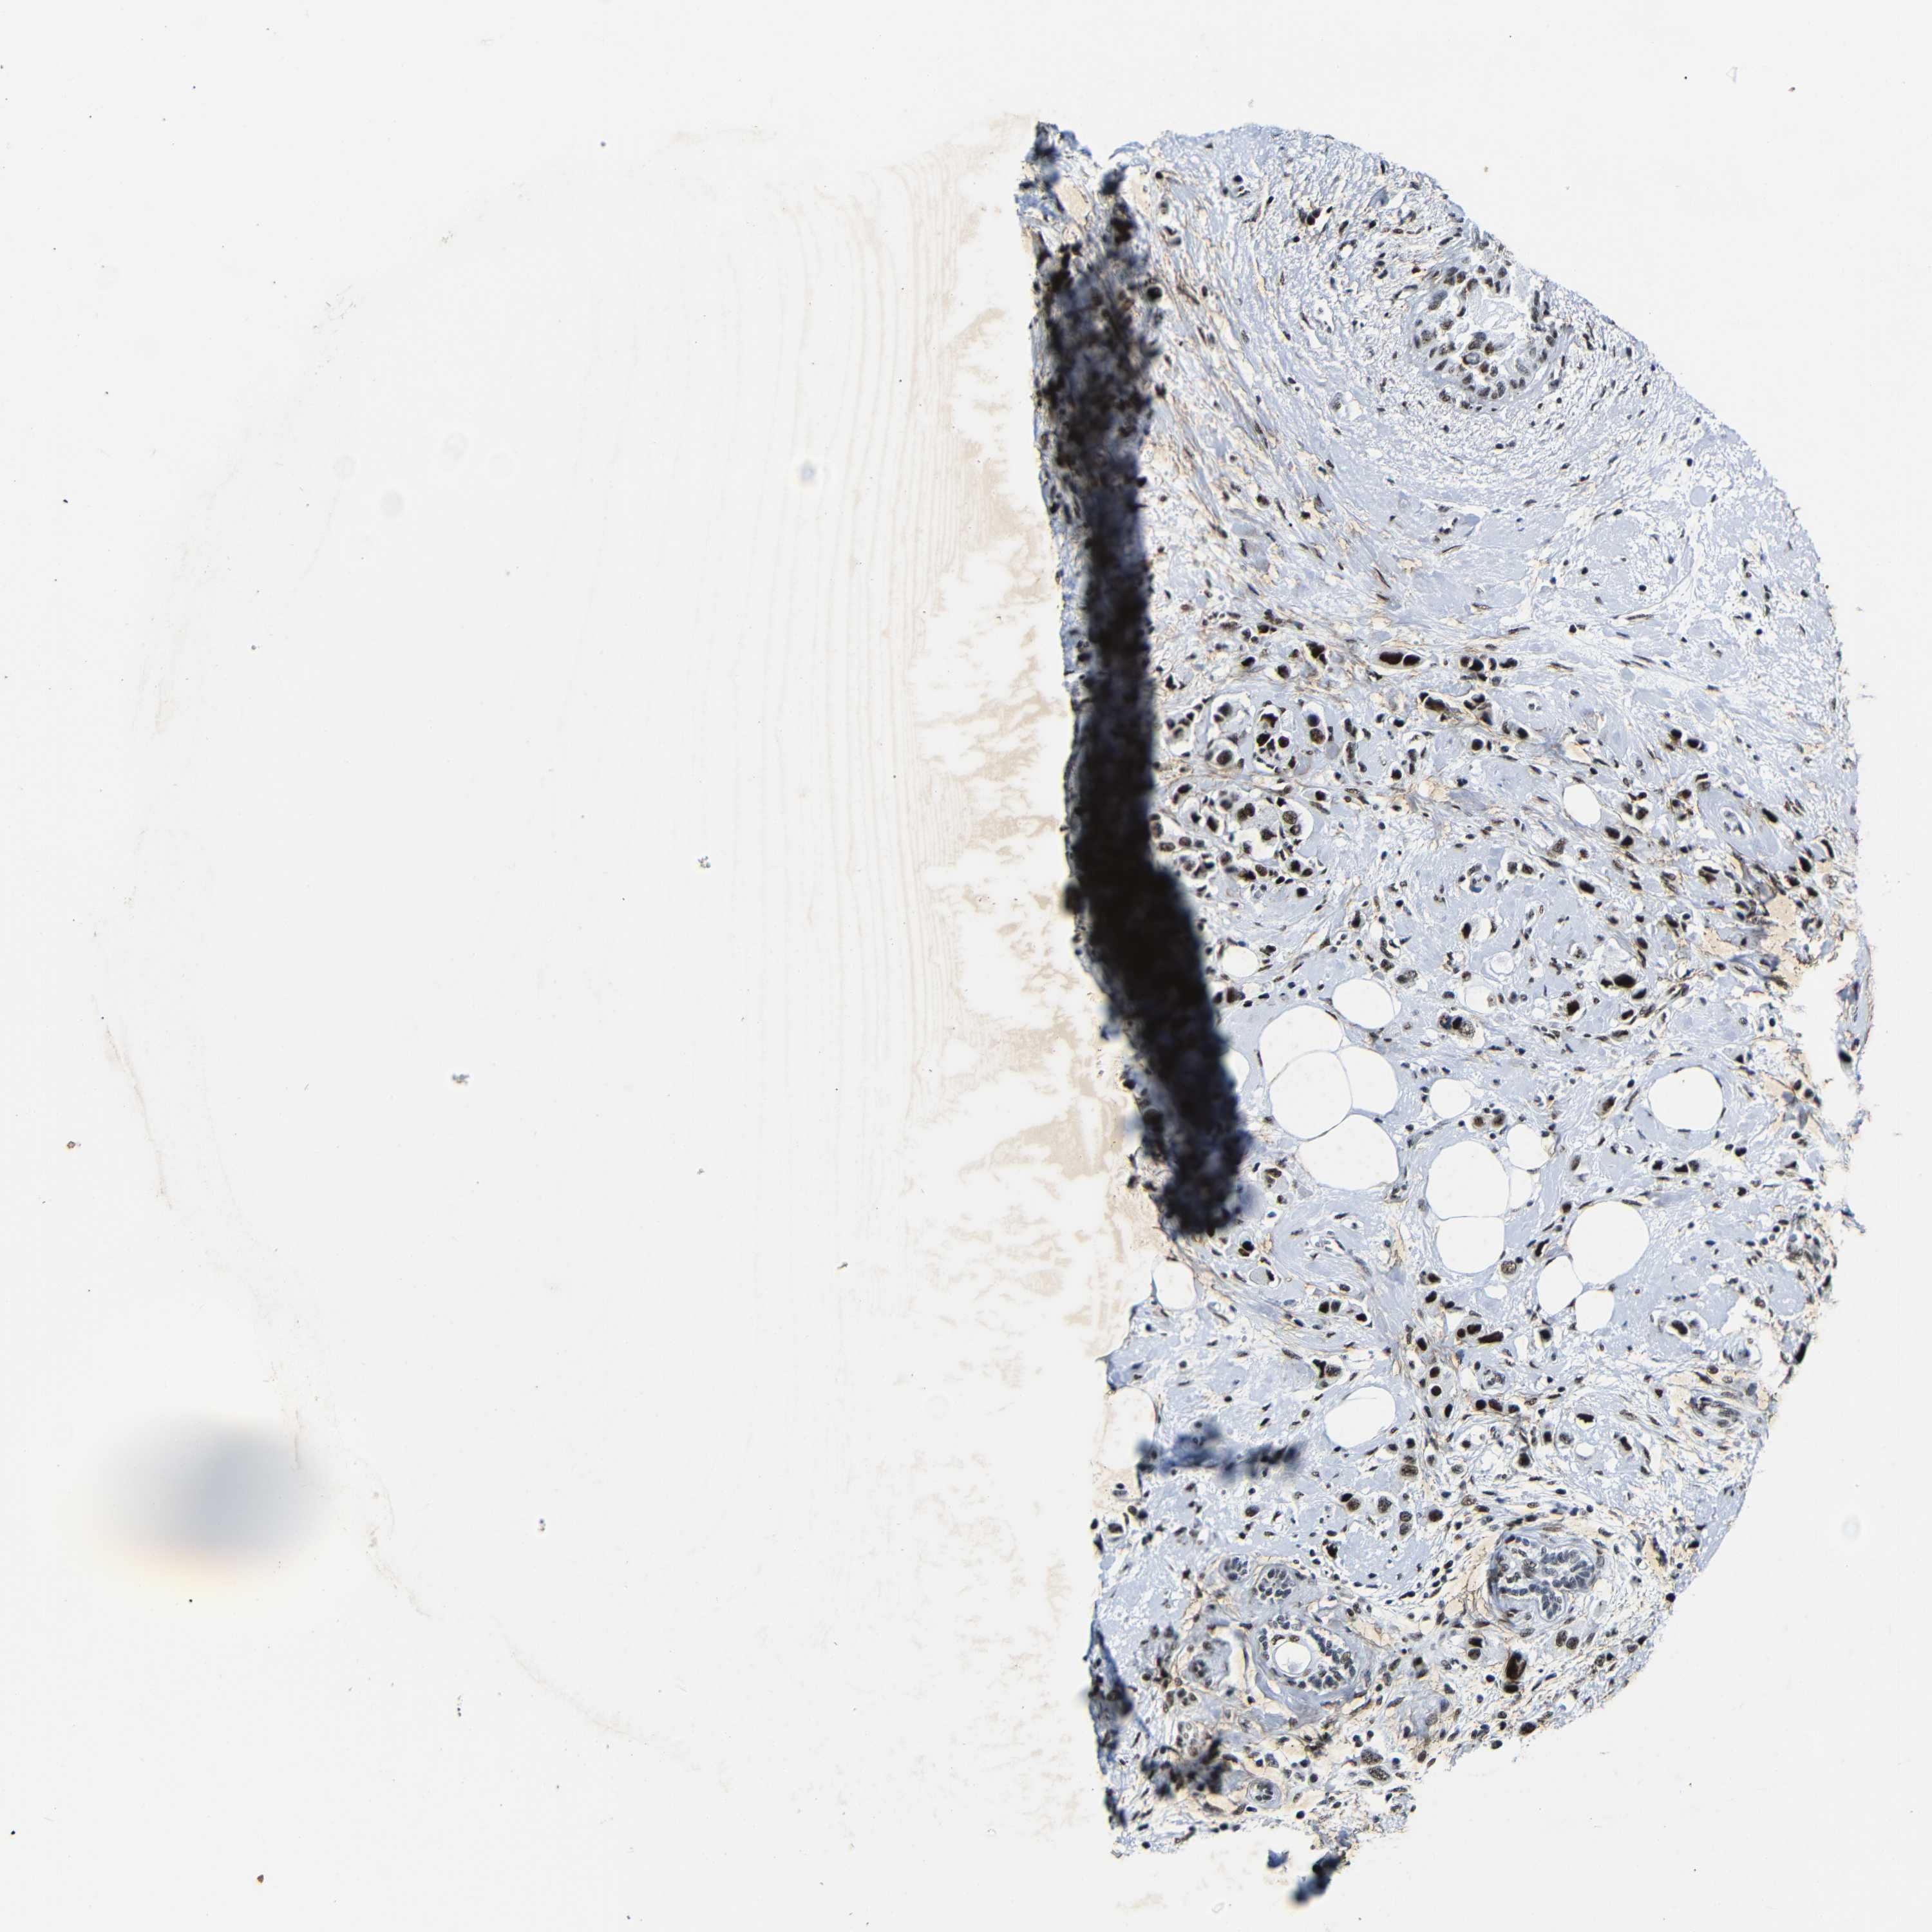

BRCA TCGA BRCA VALIDATION PROTEIN EXPRESSION